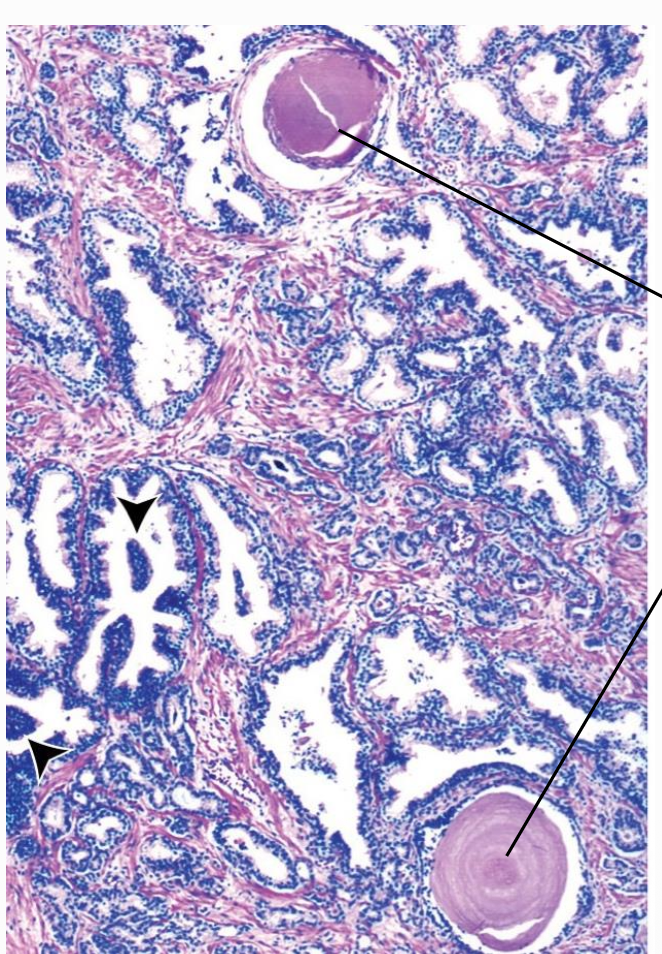

- Tubuloalveolära seromukösa körtlar omgivna av fibromuskulärt stroma (glatt muskulatur + kollagena fibrer). Trichromfärgning visar stroma blått.

- Corpora amylacea (lamellerade konkrement) ses ofta i lumen hos vuxna och ökar med ålder eller stagnerat sekret.